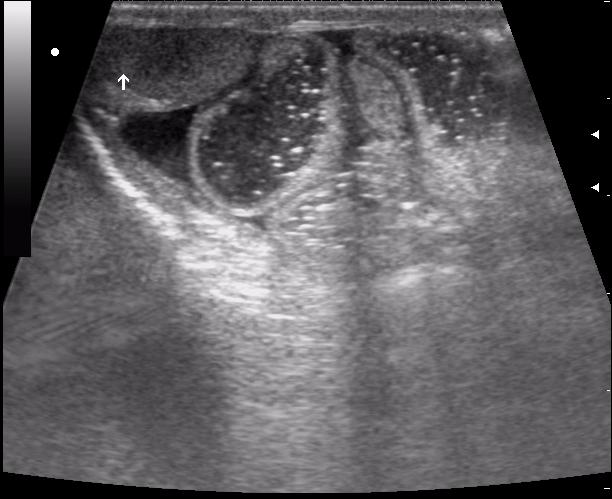

(девушке 23 года. фиброматоз матки)

Почти как на сайте Марио,только возраст другой.Солидное гипоэхогенное негомогенное образование в области придатка слева довольно сложной структуры с усилением(?) кровотока по периферии-я за рак яичника

ещё раз - это матка 23-летней девушки. то есть, ВСЁ это, то что Вы видите, да-да, на весь экран - это матка.

Диагноз - фиброматоз. направлена строго на север и налево. к соседям. (онкодиспансер)